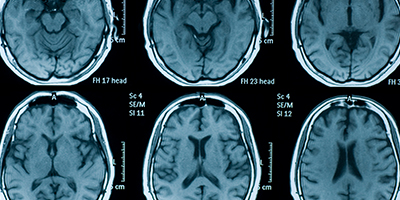

Learn how Alzheimer’s disease affects the brain.